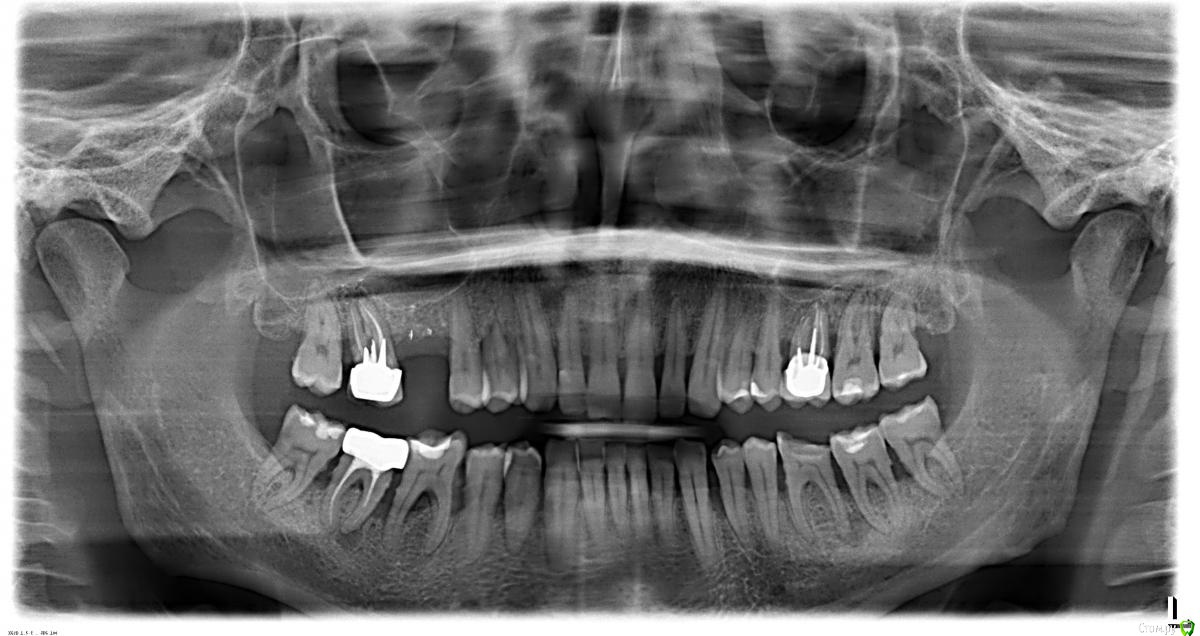

Oleg149 Опубликовано 2 октября, 2019 Поделиться Опубликовано 2 октября, 2019 Здравствуйте, Мне 45 лет, страдаю пародонтитом. Гигиену соблюдаю на высоком уровне уже более 15 лет: ирригатор, флосс, ультразвуковая щетка, спец.пасты, чистки у стоматолога каждые 6 месяцев.ОПТГ во вложении.Ссылка на кт: https://yadi.sk/d/AZ0vS9b8qC3MdQ В настоящее время прогрессирующее ухудшение состояния десен, подвижность зубов 2 степени, пародонтологические карманы 5-7 мм. Кроме этого под №36 образовалась киста со свищем в десне. Также имеются зубы с плохо пролеченными каналами: №17 и 46.1,5 года назад потерял 16 зуб после "флюса".Пародонтолог советует 5 операций открытого кюретажа (сегментарно) на 22 зуба с предварительным лечением зуба со свищем. Вопросы: 1) есть два мнения специалистов: антибактериальную терапию проводить до операции или после операции?2) ваше мнение по перспективе лечения зуба №36 (нижняя 6ка слева)3) возможно ли лечить зубы №17 и 46 с недопломбированными каналами?4) прошу порекомендовать пародонтолога-хирурга для проведения операции открытого кюретажа в Москве с демократичными ценами (желательно Новогиреево, Новокосино, Реутов )5) общие перспективы лечения, в случае удаления трех зубов №17,36,46. Какие наиболее целесообразные варианты будут: импланты, мост? И наиболее эффективные методики лечения пародонтита в таком случае для стабилизации. Прикрепленные изображения Ссылка на комментарий

stommm Опубликовано 2 октября, 2019 Поделиться Опубликовано 2 октября, 2019 консервативное лечение у пародонтолога было? Когда? И когда сделана ОПТГ?На ОПТГ видны камни и на мой взгляд любое хирургическое лечение только после полноценного консервативного с паузой и оценкой результата после него. Ссылка на комментарий

Oleg149 Опубликовано 3 октября, 2019 Автор Поделиться Опубликовано 3 октября, 2019 консервативное лечение у пародонтолога было? Когда? И когда сделана ОПТГ?На ОПТГ видны камни и на мой взгляд любое хирургическое лечение только после полноценного консервативного с паузой и оценкой результата после него.B4D6E27C-66DC-4446-ADD4-11100412D768.jpegОПТГ и КТ сделаны пару дней назад. Консервативного лечения у пародонтолога не было, только проф.чистка каждые 6 месяцев. Последнюю проф.чистку делал в конце июня в пародонтологическом центре.Под консервативным лечением вы имеете в виду антибиотикотерапию? Ссылка на комментарий

stommm Опубликовано 3 октября, 2019 Поделиться Опубликовано 3 октября, 2019 (изменено) Консервативное лечение это дохирургический этап. SRP. Надо механически (ультразвук, кареты, боры) насколько это возможно убрать все отложения из-под десны и сгладить поверхность корня. То, что я обвёл на Вашей ОПТГ. Хирургия после оценки результата при условии что консервативно уже ничего не сделать. И только на фоне удовлетворительного уровня индивидуальной гигиены. Вообщем начинайте с этого. Гигиенисты обычно под десну инструментом не заходят, и вам нужна не просто профгигиена. Изменено 3 октября, 2019 пользователем stommm Ссылка на комментарий